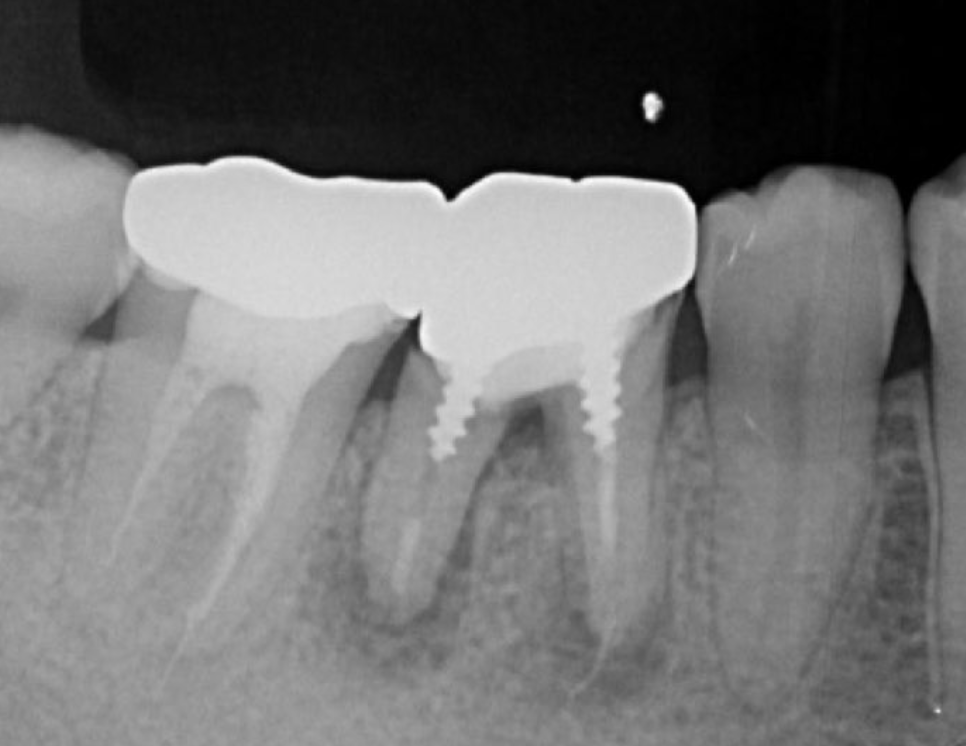

Figure 6.Dental X-ray image obtained after transplantation.

Endodontic treatment was initiated at 14 days after transplantation (8, 17). Root canal treatment for #48 was performed using Ni-Ti files (Pro Taper Next, Dentsply Sirona, Tokyo, Japan) to accommodate the complex morphology of the root canal and for minimal removal of the tooth structure during formation of the access cavity. Root canals were medicated with calcium hydroxide paste and then filled with gutta percha. The splint was also removed four weeks after the operation and a resin core was used as an abutment construction. In an attempt to appropriately modify contact and the crown morphology, a crown prosthesis was made with a full metal crown, with occlusal contact confirmed with use of a temporary crown and easy to visualize markings on occlusal paper. The full metal crown was cemented six months later (Figure 7).

Bone regeneration was confirmed before and after grafting, after root filling, and after placement of the prosthesis, based on X-ray imaging results (Figure 8). There was no pathologic mobility or pain during mastication, and the tooth showed good function. The patient was very satisfied with the treatment results (Figure 9).

Figure 8.Cone beam CT image obtained after transplantation. Bone regeneration around the grafted tooth was confirmed.

Figure 9.Dental X-ray image obtained two years after transplantation. Bone regeneration around the grafted tooth was confirmed.